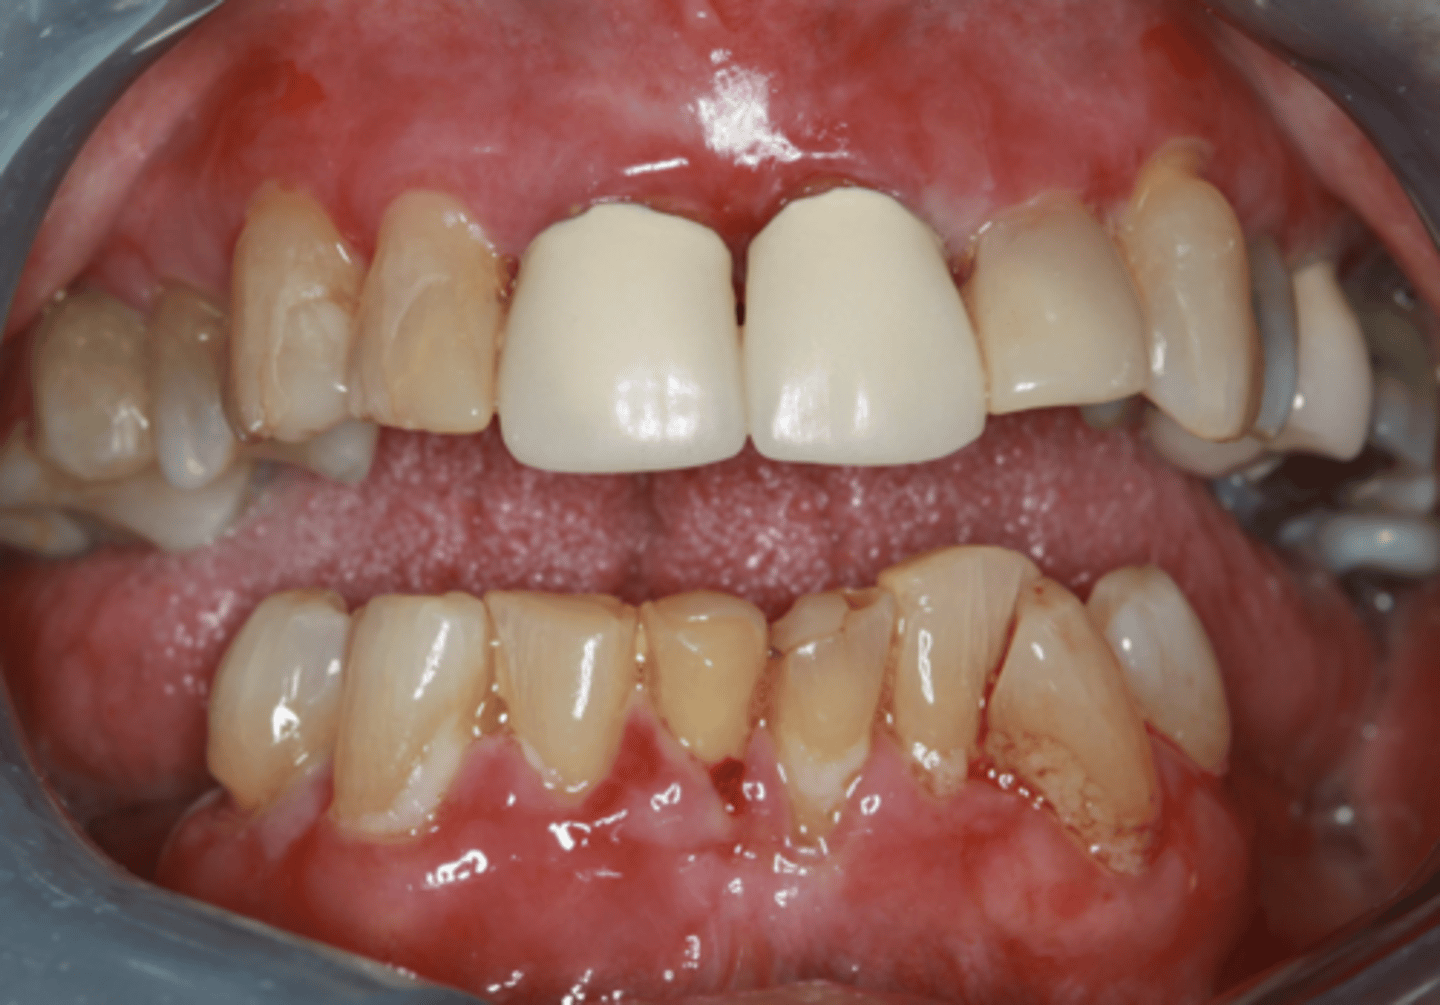

Pemphigus vulgaris (PV)

What condition?

- Painful chronic oral sores, dysphagia, weight loss

- Oral lesions

- - 50% show oral lesions first

- - Almost all show oral lesions eventually

- Positive Nikolsky sign